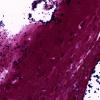

Artifact - Swiss Cheese Brain (3)